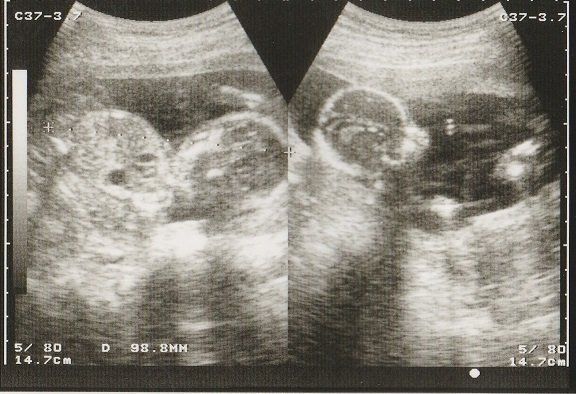

妊娠29週目のエコー写真 お母さんの体にむくみなどが出てくる時期

赤ちゃんの眼球が写っています。このころ、おなかのなかで赤ちゃんも寝たり起きたりしているそうです。

この時期になると、手足のむくみが気になるようになりました。